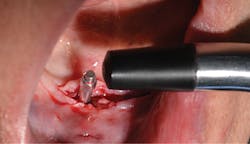

After the fabrication of full upper and lower immediate dentures, the patient underwent extraction of the remaining teeth and the placement of eight immediate dental implants (Hahn Tapered Implants, Glidewell; figure 8).

At the time of placement, ISQ readings were taken. Though the primary stability was high in these implants, the decision to allow them to integrate prior to loading was made, as each individual implant would be subjected to forces and they were not splinted. After insertion, 3-mm healing abutments were placed on all the implants except tooth No. 3, as that implant had a much lower initial stability reading. On the lower arch, 3 mm healing abutments were placed on all implants except for No. 22 due to stability. The dentures were relieved and delivered to the patient.